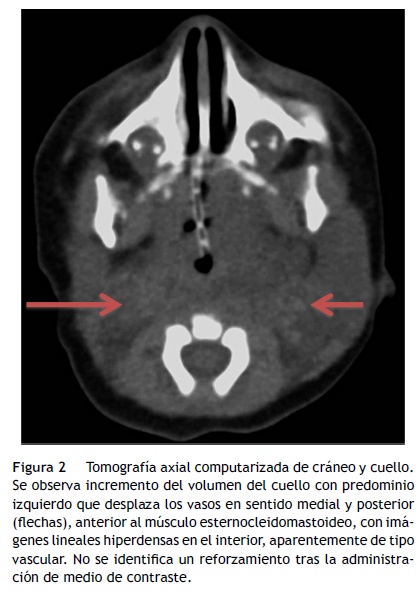

La tomografía axial computarizada (TAC) a nivel de la cara lateral del cuello mostró franca asimetría en el volumen con predominio izquierdo, a expensas de una imagen hipodensa, con atenuación aparentemente líquida, mal delimitada, que desplazaba los vasos en sentido medial y posterior, en posición anterior al músculo esternocleidomastoideo. En dicha imagen se observó involucrada la grasa del espacio parafaríngeo que desplazaba la vía aérea hacia la derecha, comprimiéndola y condicionando la disminución del calibre en más del 50% (fig. 2).